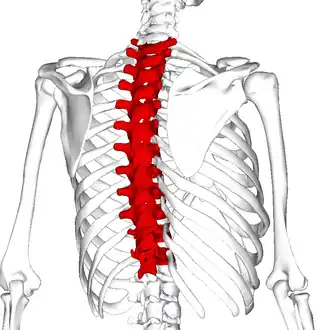

Position of the thoracic vertebrae (T1–T12) | |

In vertebrates, thoracic vertebrae compose the middle segment of the vertebral column, between the cervical vertebrae and the lumbar vertebrae.[a] In humans, there are twelve thoracic vertebrae of intermediate size between the cervical and lumbar vertebrae; they increase in size going towards the lumbar vertebrae. They are distinguished by the presence of facets on the sides of the bodies for articulation with the heads of the ribs, as well as facets on the transverse processes of all, except the eleventh and twelfth, for articulation with the tubercles of the ribs. By convention, the human thoracic vertebrae are numbered T1–T12, with the first one (T1) located closest to the skull and the others going down the spine toward the lumbar region.